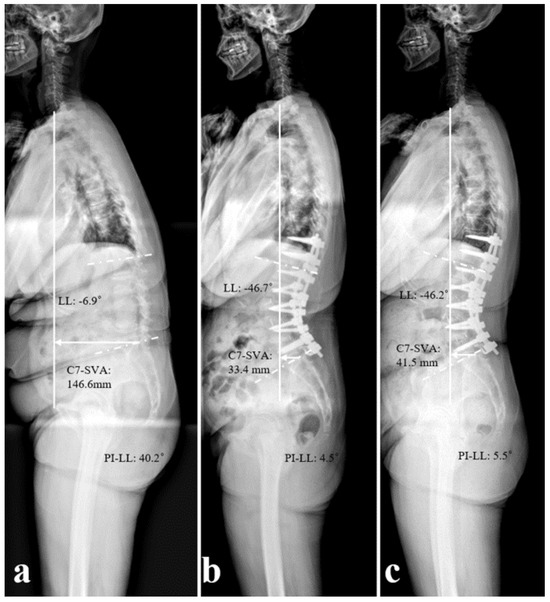

Indications of Clinical Application of L5 Laminar Hook for the Surgical Correction of Degenerative Sagittal Imbalance

by Xiongjie Li, Yong-Chan Kim, In-Seok Son and Sung-Min Kim

Medicina 2025, 61(11), 1963; https://doi.org/10.3390/medicina61111963 - 31 Oct 2025

Background and Objectives: The selection of the optimal distal level of fusion in long-level fusion surgery remains controversial. Fusion ending at L5 preserves motion but increases the risk of L5–S1 disc degeneration. The L5 laminar hook has been introduced to enhance distal [...] Read more.

Background and Objectives: The selection of the optimal distal level of fusion in long-level fusion surgery remains controversial. Fusion ending at L5 preserves motion but increases the risk of L5–S1 disc degeneration. The L5 laminar hook has been introduced to enhance distal fixation, but its indications and clinical effects remain unclear. This study aimed to investigate the indication of the L5 laminar hook and its effect on adjacent segment degeneration when performing long-level fusion terminating at L5 in patients with degenerative sagittal imbalance (DSI). Materials and Methods: 112 patients with DSI who had undergone corrective surgery and ended at L5 were analyzed retrospectively. Finally, 64 were treated with an L5 laminar hook (Group I), while 48 were not (Group II). We compared radiographic spinopelvic parameters between the two groups and followed up disc degeneration at the L5–S1 level. Additional analysis was conducted within Group I to determine the indications for L5 laminar hook. Results: Preoperative C7 sagittal vertical axis (C7SVA), lumbar lordosis (LL), and pelvic incidence (PI)-LL mismatch were significantly greater in Group I than in Group II (p < 0.05). At 2 years of follow-up, advanced L5–S1 disc degeneration had developed in 14 patients (21.9%) in Group I and 36 patients (75%) in Group II. Patients in Group B (exacerbated L5–S1) had a significantly higher body mass index (BMI), larger preoperative C7SVA, and PI-LL mismatch than patients in Group A (preserved L5–S1). The C7SVA and PI-LL mismatch cut-off values for Group A were 15.8 cm and 40.8°, respectively. Conclusions: L5 laminar hook helps to reduce disc degeneration at the L5–S1 level and can be used to maintain the deformity correction ending at L5 in patients with DSI. We propose a series of indicators for the use of L5 laminar hooks in patients with DSI: a low BMI, a PI-LL mismatch < 40.8°, and a C7SVA < 15.8 cm. Full article

Show Figures

Figure 1